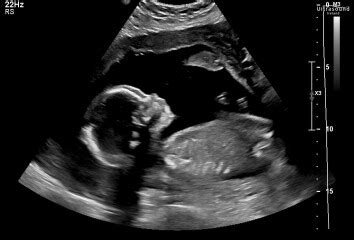

Hey everyone! So, you’re heading in for that big 20-week anatomy scan, right? It’s super exciting because you finally get to see your little one in all their glory, checking out all those tiny fingers and toes. But let’s be real, sometimes this scan can bring up some unexpected news, and it can be a bit nerve-wracking. We’re talking about findings that might seem a little scary, like ‘oscpseudosepsis sc show common’. While that specific phrase might sound like a mouthful and a bit alarming, it’s generally referring to common variations or minor findings that pop up during this detailed check-up. The good news is, most of the time, these aren’t signs of anything serious. This article is all about demystifying what these common ‘bad news’ findings at your 20-week scan actually are, what they mean for you and your baby, and what the next steps usually involve. We want to arm you with information so you can feel more prepared and less anxious if something unexpected is found. Remember, these scans are designed to be thorough, and finding something is often just part of ensuring everything is developing as it should be. We’ll break down some of the more frequently seen, less concerning issues, and help you understand the process better. So grab a cuppa, get comfy, and let’s dive into understanding those 20-week scan findings, shall we?

The 20-week anatomy scan, also known as the mid-pregnancy ultrasound, is a really important milestone in your pregnancy journey. It’s much more than just a chance to find out if you’re having a boy or a girl (though that’s a fun bonus!). This detailed ultrasound is performed by a trained sonographer or radiologist to meticulously examine your baby’s physical development. They’re looking at everything from the brain and heart to the spine, stomach, kidneys, and limbs. The primary goal is to check for any potential birth defects or developmental abnormalities. It’s a screening tool, guys, meaning it helps identify babies who might need further testing or specialized care after birth. So, when they talk about ‘oscpseudosepsis sc show common’, they are likely referring to findings that, while visible on the scan, are often benign or resolve on their own. It’s crucial to remember that a finding on a scan doesn’t automatically mean there’s a problem . It often means further evaluation is needed to confirm what’s going on. Think of it as the scan being super thorough and picking up on things that might otherwise go unnoticed until later. The sonographer will measure various parts of your baby’s body and compare them to standard growth charts. They’ll also examine the placenta’s location and the amount of amniotic fluid. This comprehensive check is why it’s so vital. However, the sheer detail can sometimes lead to the discovery of ‘soft markers’ – minor variations that are commonly seen in healthy pregnancies but can occasionally be associated with certain conditions. These soft markers are often what people mean when they report ‘bad news’ from a scan. It’s all about gathering information to ensure the best possible care for you and your baby throughout the rest of your pregnancy and beyond. So, while the scan is incredibly valuable, try not to get too hung up on every little detail you might hear – the bigger picture and the overall assessment by the medical professionals are what truly matter.